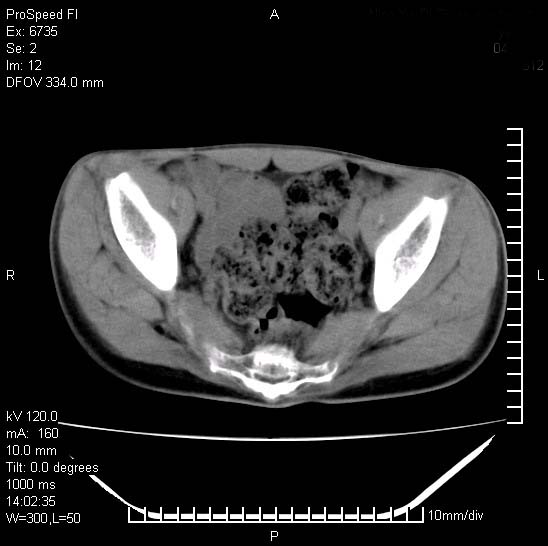

患者自诉胯部疼痛两年余,在当地服用中药,半月前至本院考虑骶髂关节结核,给予抗痨治疗。现发展至右下肢疼痛明显,活动受限,以膝关节处明显,拍膝关节平片无明显异常。

两侧骶骼关节改变,考虑强直性脊炎

左侧骶髂关节面限局性骨破坏,边缘硬化关节腔见钙化物;不出外tb

考虑强直性脊炎,建议查hla-b27

右侧骶髂关节也有类似改变,只是较左侧轻,首先考虑强直性脊柱炎,不除外结核,建议作hla-b27检查。

典型强脊炎改变,髋关节亦有累及

符合强直性脊柱炎表现。